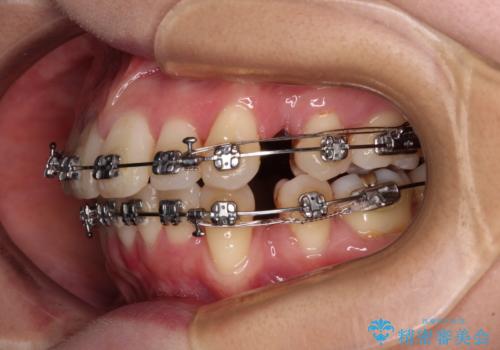

- 矯正装置

- メタルブラケット

- 八重歯と上の前歯が出っ歯になっていることを気にして来院された患者様です。

横から見た際の口元の飛び出した印象も改善したいとのことで、上下左右の第一小臼歯4本を抜歯し、ワイヤー装置にて抜歯矯正を行うこととしました。

前歯の変色している歯は、神経組織が壊死していたため、矯正治療前に根管治療を実施し、矯正治療後にオールセラミッククラウンにて補綴治療を行うこととしました。

順調に歯が動き、補綴治療も含め2年弱で治療を終えることができました。